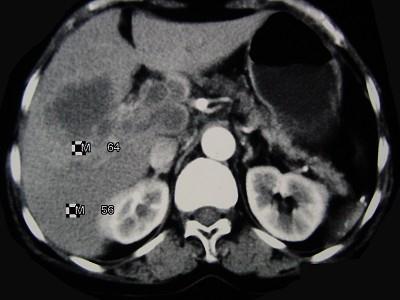

问题 女,65岁,右季肋区疼痛二个月,CT扫描所见如图,最可能的诊断是()

选项 A.慢性胆囊炎 B.胆囊癌腹膜后淋巴结转移 C.胆管细胞癌 D.胆囊黄色肉芽肿 E.胆囊腺肌增生症

答案 B